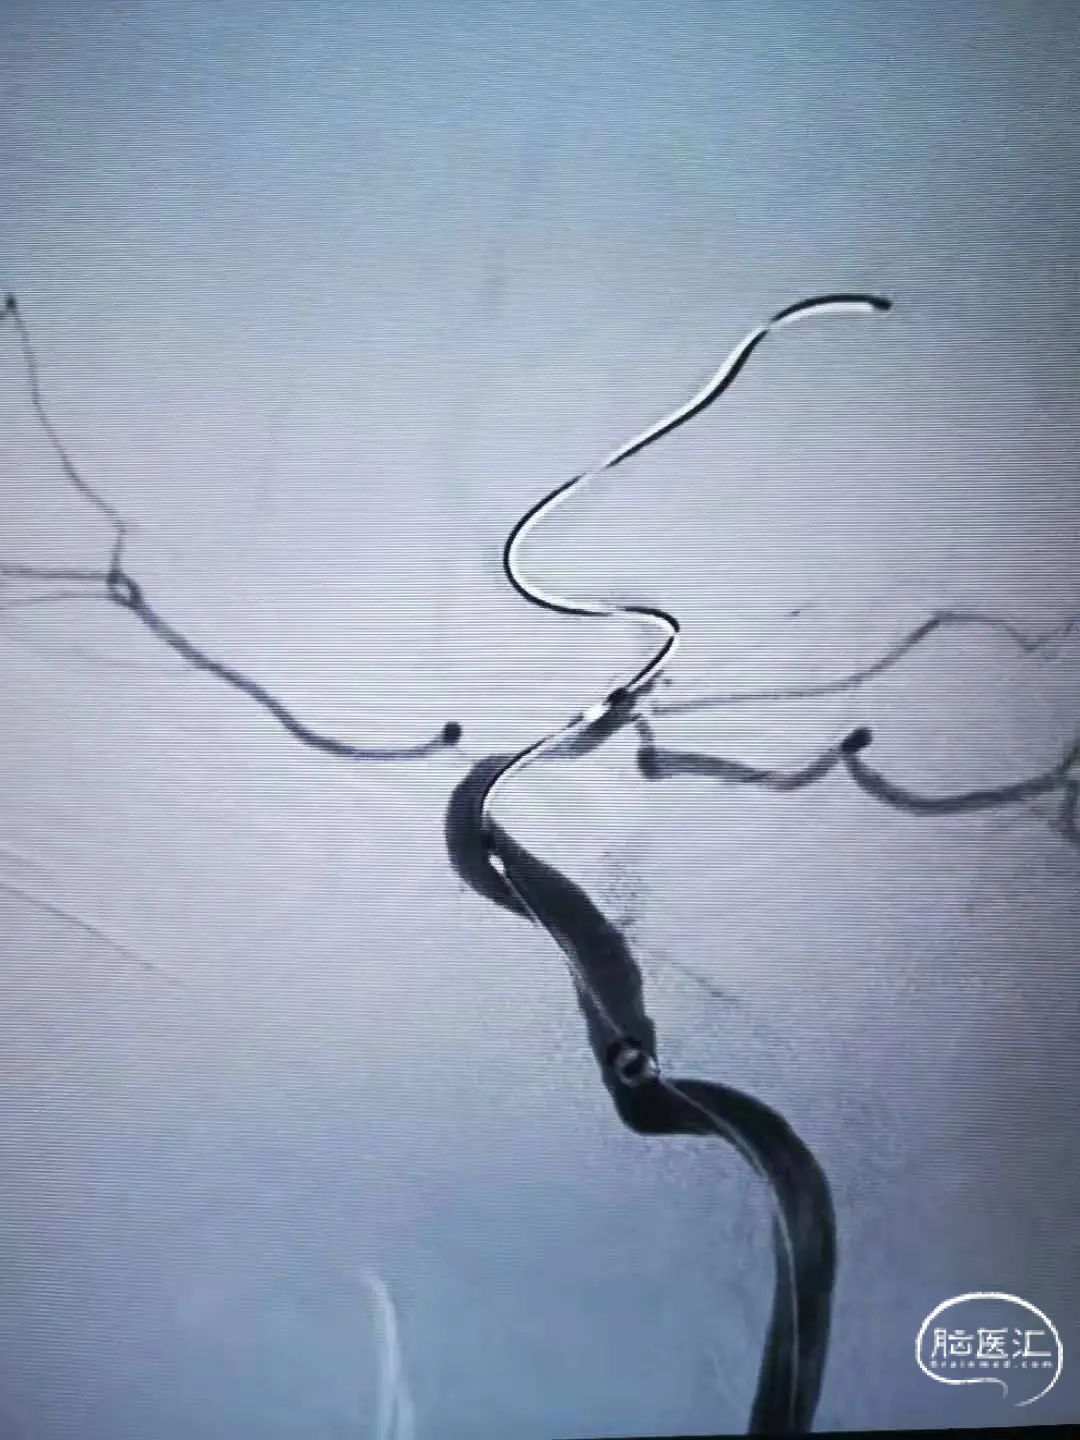

2.0×9mm球囊扩张,可见残余狭窄较重。

二次球囊扩张后可见狭窄明显改善,血流速度增快。

植入3.5×15自膨支架。

工作角度造影示:支架完全打开,贴壁良好。